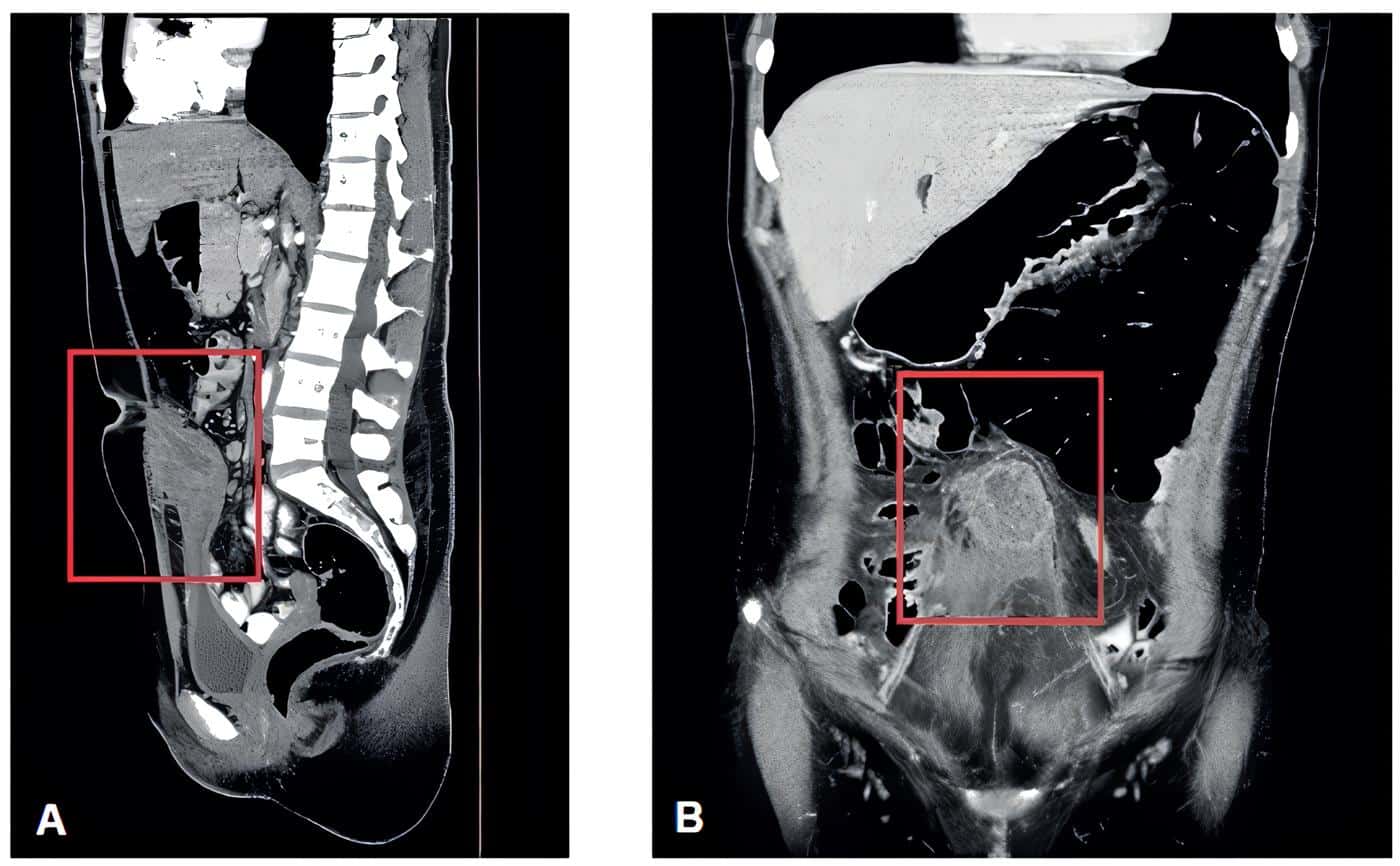

Posteriormente realizaron TC abdominal total simple y contrastada (Figura 1) que mostró masa intraperitoneal extendiéndose desde la región umbilical hasta la pared superior de la vejiga, perdiendo los planos de clivaje, y masa anexial derecha de aspecto inespecífico, sugiriendo como primera posibilidad un uraco persistente.

Figura 1. A – Vista sagital. Masa intraperitoneal extendiéndose desde la región umbilical y hasta la pared superior de la vejiga perdiendo los planos de clivaje. B. Se observa colección de 61x52x40 mm a nivel infraumbilical, intraperitoneal. Fuente: Imagen compartida por la paciente.